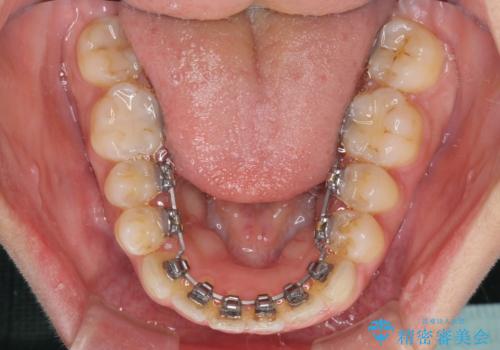

- フルリンガル

- 1年10ヶ月

- 10-30回

下顎が左側にずれているため、裏側矯正ということもあり咬み合わせを整えるのに時間がかかってしまいました。